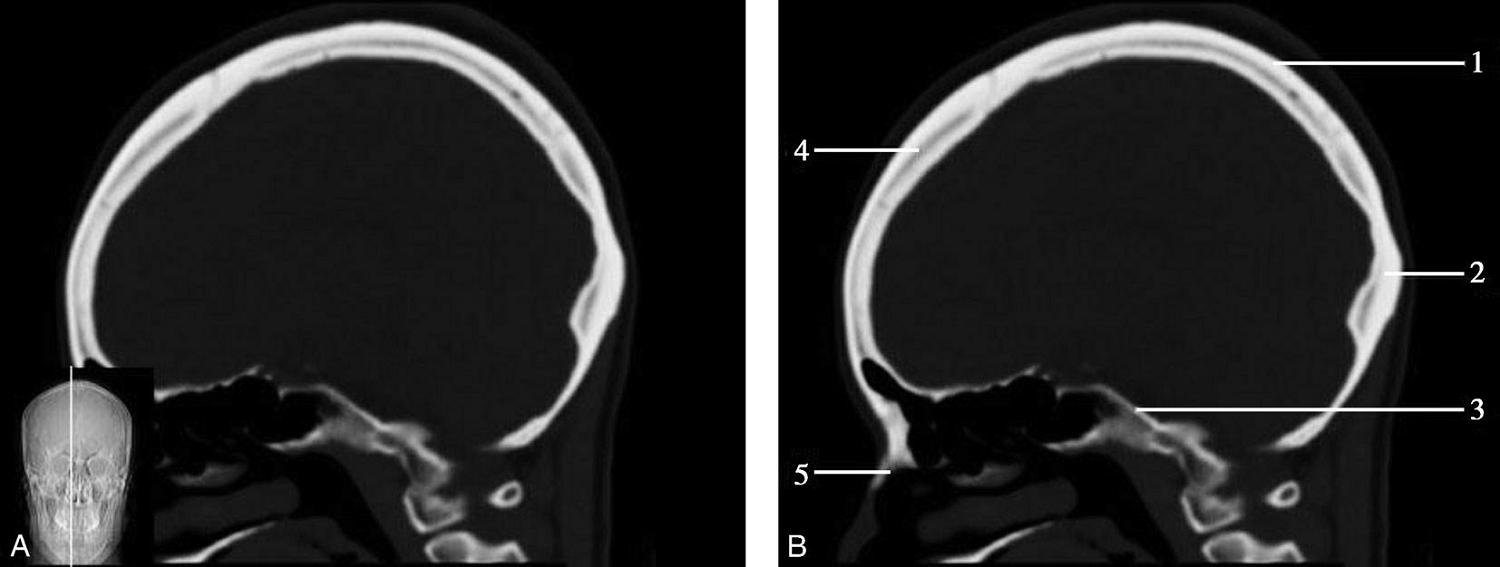

图1-2-60 正中矢状面骨窗CT

A.矢状面;B.矢状面标注

1.顶骨;2.枕骨;3.斜坡;4.额骨;5.蝶鞍

此层面可显示胼胝体全貌,它位于层面中央区域,是呈上凸下凹的弧形结构,由前向后分为嘴、膝、体和压四部分。扣带回环绕胼胝体上方,扣带沟位于扣带回的上方。大脑半球中部和后部分别可见较深且恒定的中央沟和顶枕沟。中央沟为是额叶顶叶分界标志。

胼胝体下方为侧脑室及穹窿,第三脑室借穹窿与前上方的侧脑室体部分开,背侧丘脑的内侧面以及中脑顶盖分别为第三脑室的外侧壁和底。第三脑室向前籍室间孔与侧脑室相通,向下经中脑导水管通第四脑室。中脑腔狭窄呈管状,即称为中脑导水管,中脑导水管畸形,常见者为导水管的分叉畸形和狭窄,其次可见中脑导水管膈膜,造成先天性脑积水。

脑干由中脑、脑桥和延髓组成,自第三脑室底向下后稍斜行,移行于颈髓。由上至下,脑干腹侧可见脚间池、桥前池和延髓池,脑干背侧可见大脑大静脉池、四叠体池和小脑延髓池。

垂体位于蝶鞍内,其前部为腺垂体,后上部分为神经垂体。垂体下方为鞍底及蝶窦,上缘因鞍膈存在而平直,垂体借垂体柄向上连于丘脑下部。垂体的前上方见视交叉和视束。斜坡作为前颅窝底的重要组成部分与多个重要结构相比邻,矢状位呈三角形,颅内肿瘤或颅外鼻咽部恶性肿瘤均可侵犯至此,原发肿瘤常见为脊索瘤。小脑幕居枕叶和小脑之间,向后下连接窦汇,向前至中脑后方游离,称小脑幕切迹。小脑幕下方为小脑扁桃体。成年人小脑扁桃体下缘由枕骨大孔向下疝入椎管超过5mm称为Chiari畸形,以矢状位显示最佳。